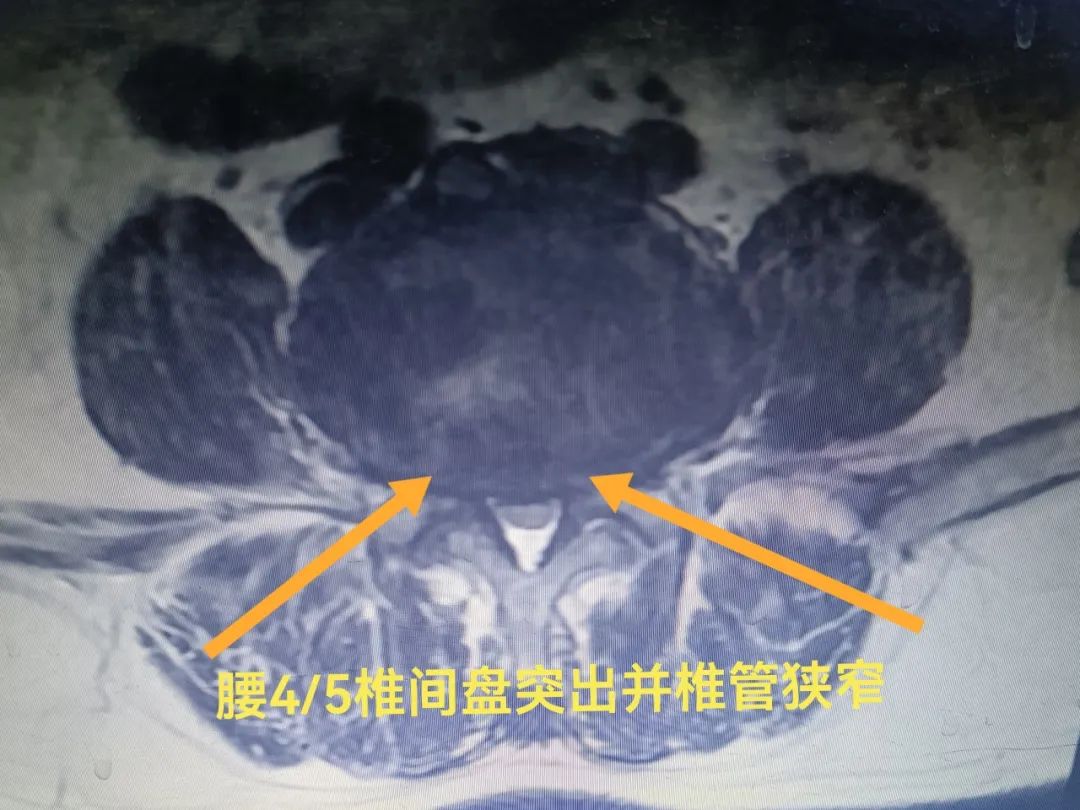

殷先生为求进一步治疗,来到宁阳县第一人民医院康复二科门诊,经康复二科副主任王阳检查后,结合影像资料,诊断为腰椎间盘突出伴神经根病。

王阳在C型臂透视导引下,对病灶位置精准定位后,通过几毫米的穿刺针将医用三氧注入L4/5椎间盘,随后行腰椎侧隐窝注射术,用侧隐窝穿刺针注入消炎镇痛液,手术仅用半小时就顺利完成。术后,殷先生明显感觉到疼痛减轻,第二天就可正常走路,对微创三氧治疗非常满意。